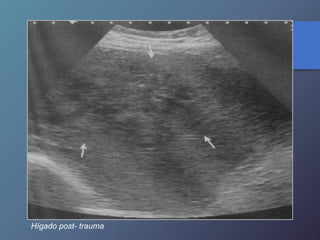

Traumatismo Hepático

• La lesión hepática es a predominio del lóbulo derecho.

• Mayor particularidad en segmento posterior.

• Mayor frecuencia por laceración peri vascular.

• Se producen hematomas subcapsulares,

pericapsulares o aislados.

• La hemorragia en las primeras 24 horas es ecogénica y

posteriormente se hace mas hipoecogénica.

• Entre las dos o tres semanas se puede observar gran

cantidad tejido de granulación.

Hígado post- trauma

Hematoma sub capsular hepático